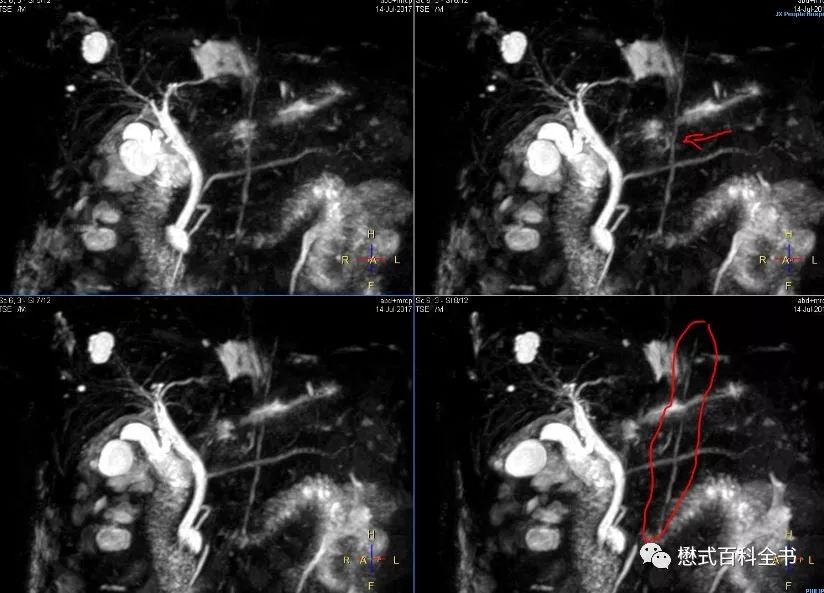

图8:Biliary normal variants and artifacts, Radiology 2015

图9:MRCP注意看图中标记的线

有时候,我们组MRCP经常能看到一根比较亮的线竖着穿过胰管。有老师认为是伪影,有老师认为是其他结构。看了一些文献,有的说这个是淋巴管,扫描MRCP出现这个的概率不多。还有文献说和人种有关系,貌似中国人出现这个多。这个位置看着是胸导管?(我们专门有针对胸导管成像的序列,效果非常好)对于这个问题,我也没有过多研究,看看老师们有什么高见,可以留言。